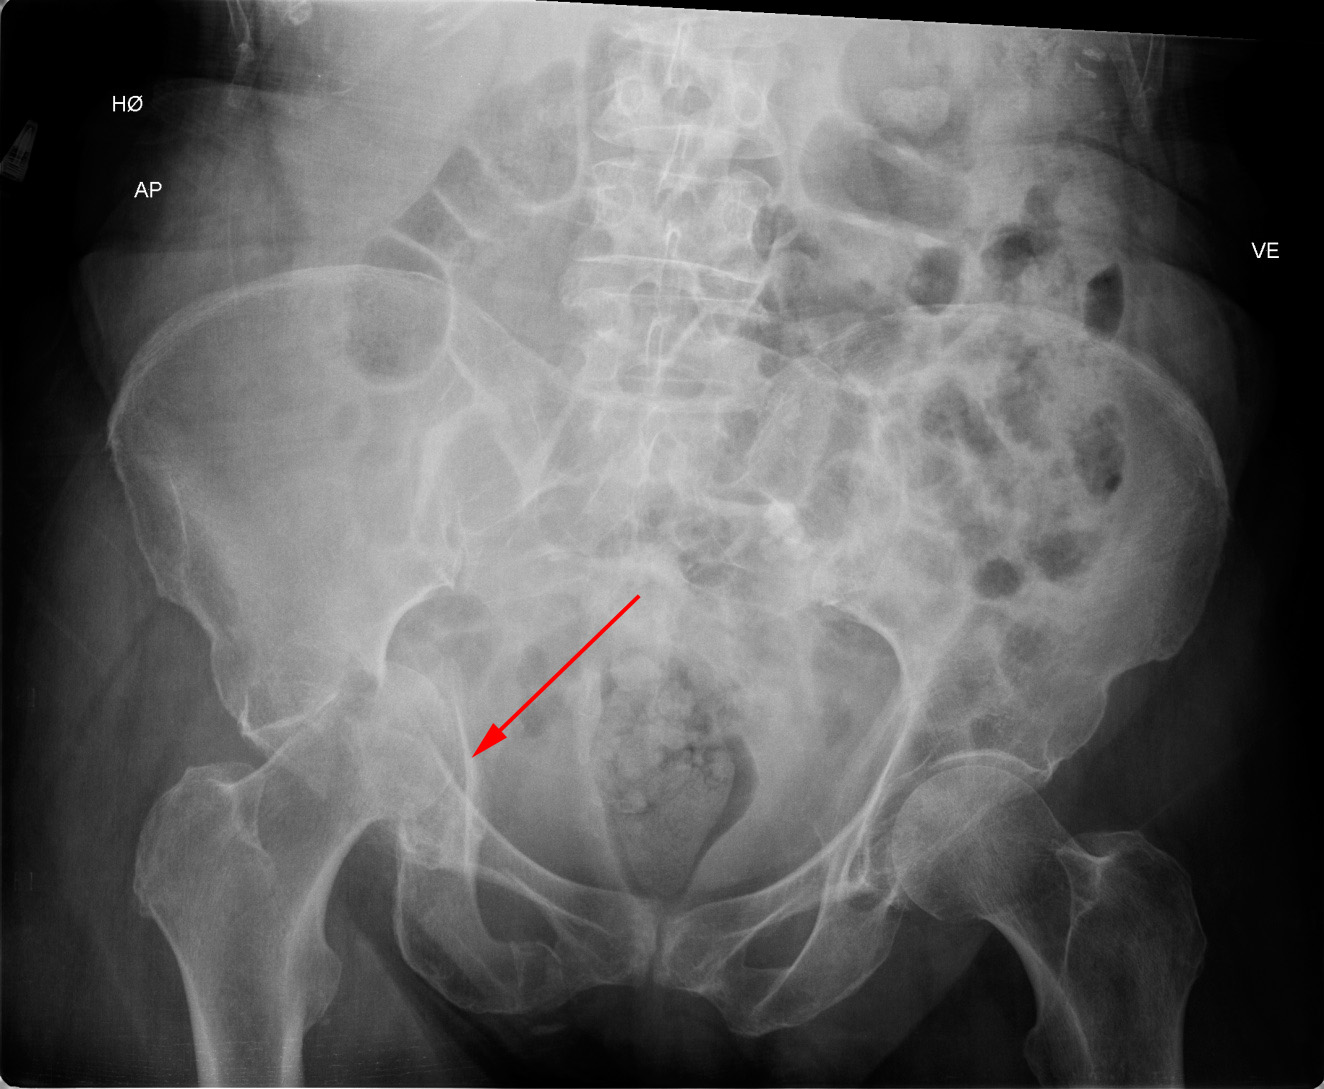

Røntgenbillede af bækkenet, som viser knusningsbrud af hofteskålen (acetabulum).